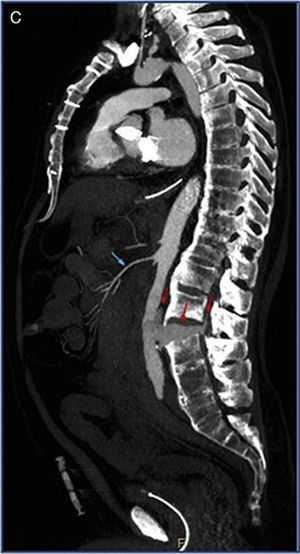

Fifty-six year-old anticoagulated male with ankylosing spondylitis hospitalized after being struck by a car. Patient presents in the hospital with hypovolemic shock, requiring massive blood transfusion and the administration of vasoactive drugs. Negative echo-FAST. The CAT scan confirms aortic rupture secondary to spinal lesion due to a flexion-distraction mechanism. Figures 1 and 2 show axial slices with IV contrast (IVC) in the arterial phase (A), portal phase (B), and sagittal slices in the arterial phase (C) at L2-L3 level. The abdominal aorta shows abundant adjacent hyperdense material consistent with extravasated IVC material (arrows) in the retroperitoneum, the intersomatic space and the epidural space. Patient undergoes urgent surgery that is followed by perioperative death (Figures 1 and 2).